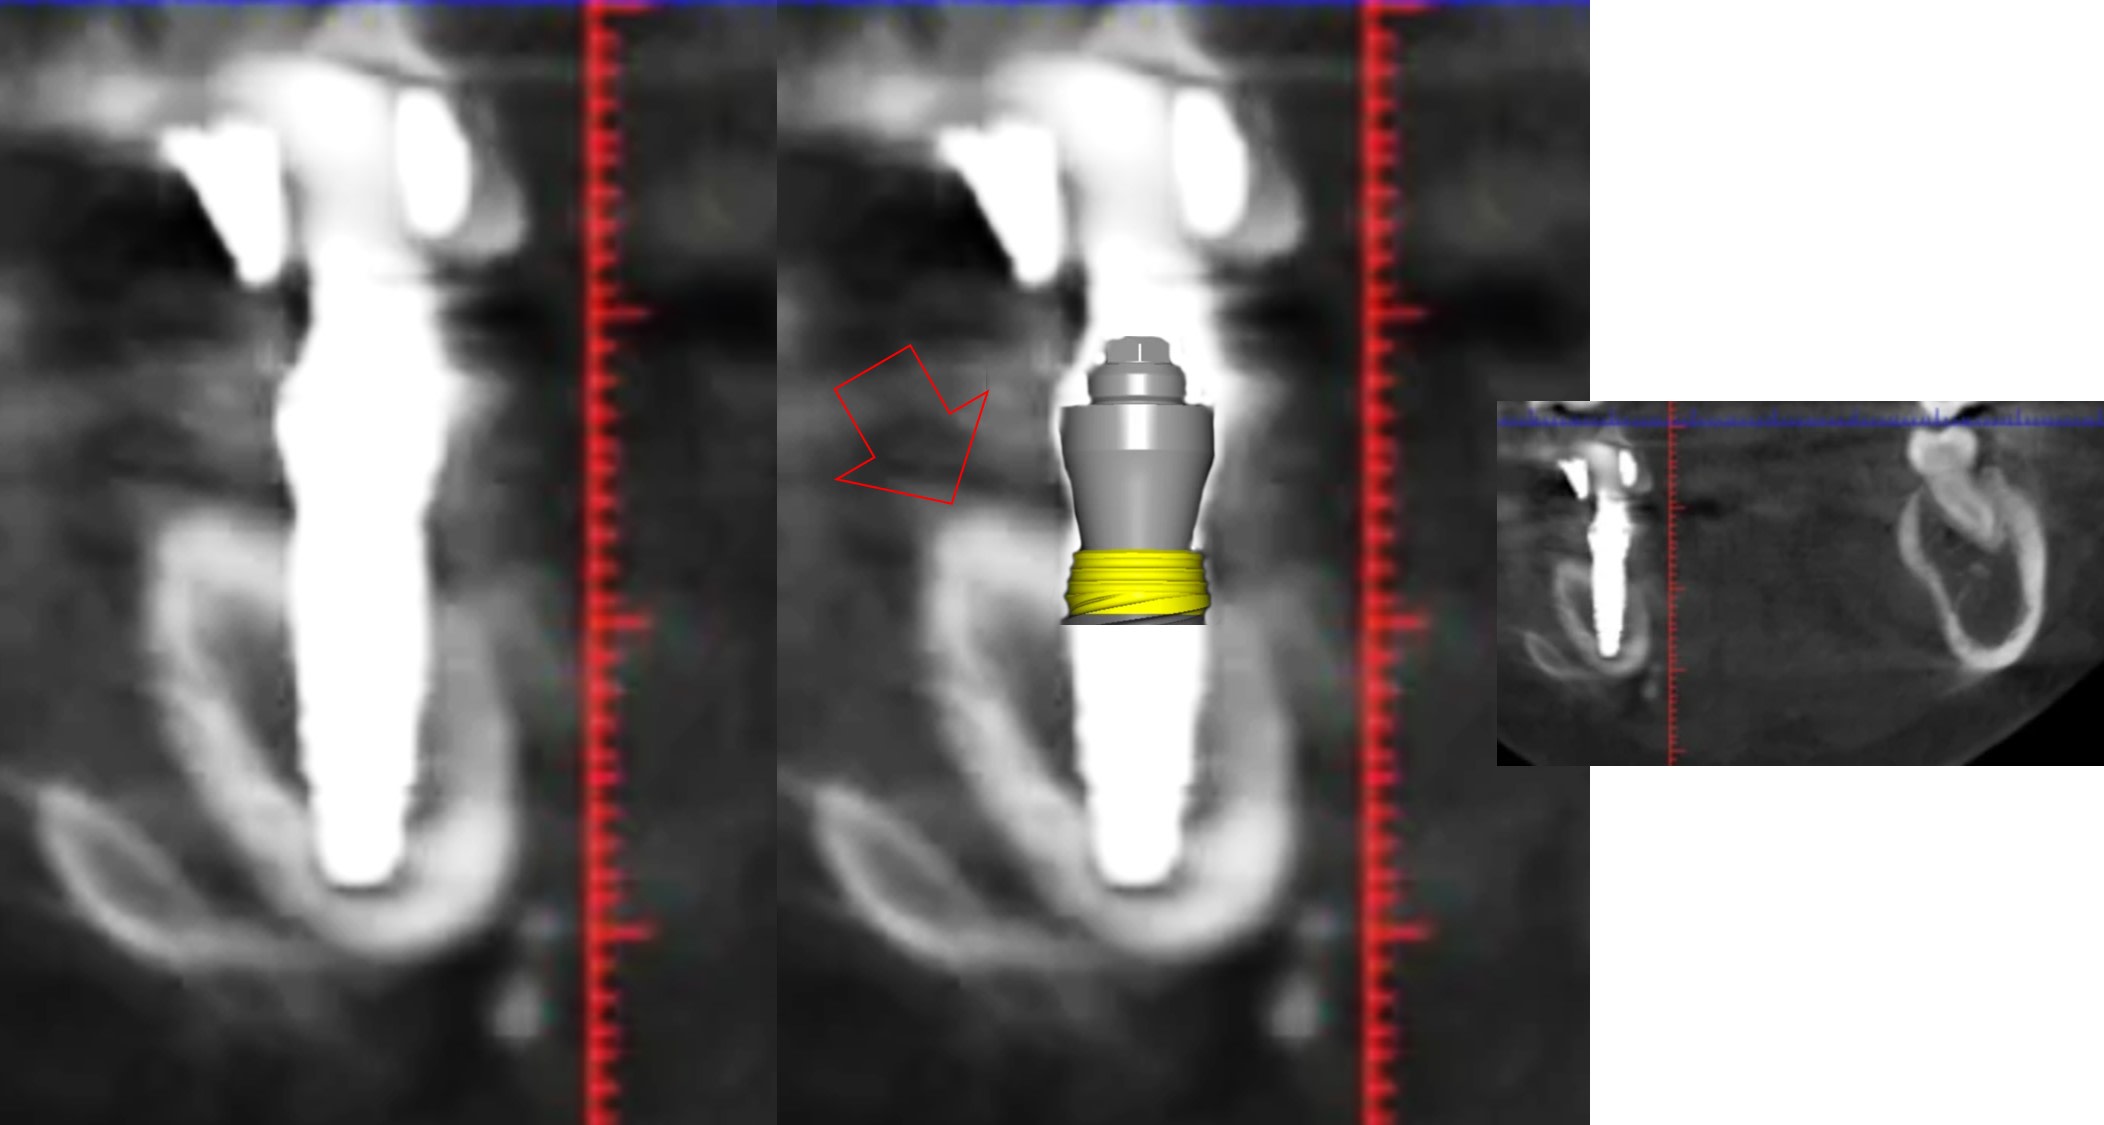

1 se baser sur la pano pour en tirer des conclusions est une erreur de débutant

2 sur les coupes scanner une partie du col est infra osseuse et l'autre non

3 lorsque tu te permets le genre de commentaire que tu fais il faut être en mesure d'étayer un argumentaire

mais posit... y'a que toi qui pense que l'implant est aussi enfoui... ca saute aux yeux que tu fais tout pour grater 1mm d'enfouissement... pour qu'ils paraissent pas si mal posé que ca...

avec, par exemple, ton implant de 10mm qui est contenu dans 9mm... t'es le Gérard Majax des guides chir.

comme ici... si e carré fait 4,5 alors l’implant ne fait pas 10 mais moins de 9...

Tout comme l’autre implant pas 11,5 mais 10,3

heureusement que ta méthode est "précise" ;)

En traçant le col de l'implant comme tu le fais tu ne tiens pas compte que le pilier fait 4,5 mm de hauteur, normalement tu devrais arriver à le comprendre tout seul !